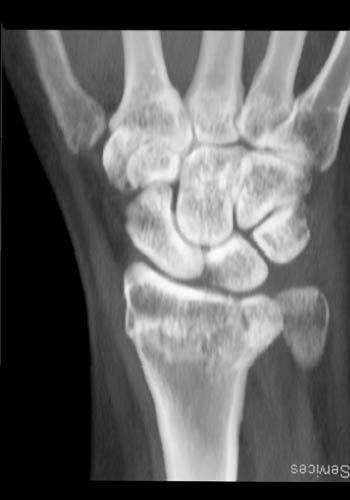

The distal radius is most commonly fractured in older women, particularly those with osteoporosis. The younger patient may sustain a distal radius fracture in the setting of severe trauma. In many cases, these fractures are readily apparent on conventional radiographs. However, subtle fracture may not be evident, and CT should be considered to detect these in patients with a high clinical suspicion and a negative radiograph. CT provides a comprehensive evaluation of distal radius fractures and has been shown to impact treatment plans for intra-articular radial fractures.

Goldfarb's article entitled “CT of the wrist: What the clinician wants to know” provides an outstanding overview of how radiologists should approach wrist fractures. He provides a thorough summary of the classification systems for distal radius fractures. Most importantly, he clearly elucidates the specific findings which must be detailed in the evaluation of distal radius fractures. The following features should be described: the type of fracture (transverse, oblique, depressed), angulation, displacement, presence of comminution, intraarticular extension (radiocarpal or distal radio-ulnar joint, evidence of ligamentous injury and the presence and location of an unlar styloid fracture.

Intra-articular extension is reported to occur in 50-81% of distal radius fractures. If identified, a detailed description of the location and appearance must be provided. The radiocarpal articulation (at the scaphoid and lunate fossa), the radioulnar articulation (at the sigmoid notch) or the ulnar styloid may be involved. Careful inspection must be made to detect any step-off in the articular region of the radiocarpal joint or gaps, because these have prognostic value for the development of radiocarpal osteoarthritis. The presence of articular incongruities measuring more than 1-2 mm after closed reduction is felt by many to be an indication for surgical reduction to prevent disabling osteoarthritis an d maintain wrist function. CT has been shown to be superior for measuring the articular gapping, with substantially larger measurements compared to radiographs. Furthermore, radiographs underestimate the degree of comminution and DRUJ involvement. With respect to articular step-offs, one study by Katz showed no significant difference between CT and radiographs for quantification; however, Pruitt demonstrated that determination of t he extent of articular surface depression was better with CT.

An ulnar styloid fracture is present in 51-65% of distal radius fractures. Fractures of ulnar styloid are important to identify and localize because of the associated ligamentous injuries. The triangular fibrocartilage complex (TFCC) attaches to the ulnar styloid, and the dorsal and volar radioulnar ligaments attach to the base. The fracture size and the degree of displacement both correlate with the development of DRUJ instability. In ones series, all distal radius fractures which developed DRUJ dysfunction had a concomitant ulnar styloid fracture. Fractures of the base had the highest incidence of DRUJ instability.